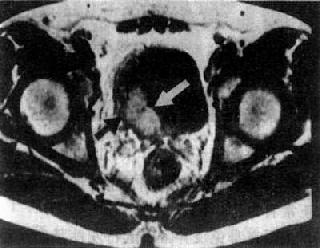

图4-4-10 膀胱癌 (二)前列腺肥大与前列腺癌 前列腺的大小同年龄有关,但一般其直径不超过5cm。前列腺肥大可,见前列腺向膀胱底突入。边缘光滑,密度均匀,一般是两侧对称,便可一侧肥大明显。冠状面显示更为清楚。 前列腺癌在包膜内生长时,CT难于确诊,只有当侵破包膜向周围脂肪组织中浸润时才可能诊断。表现为前列腺轮廓不整,密度不均。直肠前壁及膀胱壁可被浸润,精囊角消失。CT还可发现淋巴结转移和盆骨转移。CT对前列腺癌的分期有帮助。 MRI上,因前腺增生主要发生于中央区,故T2WI上显示中区央增大。而前列腺癌多发生于周围区,致使周围区在T2WI上信号有局限低或稍低信号的结节影。因此MRI比CT更具诊断价值。但前列腺癌的MRI表现不典型时,诊断仍较困难。 (责任编辑:泉水) |